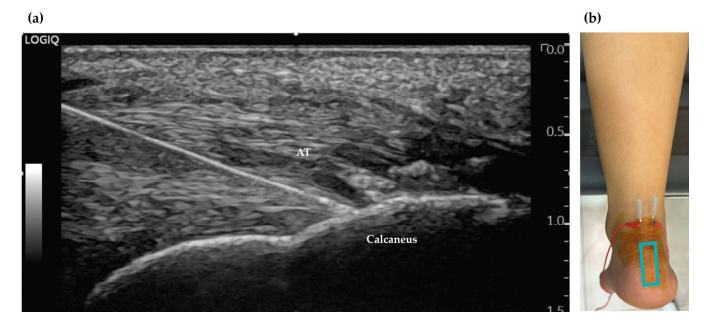

발목 외측의 곤륜혈(崑崙, BL60)에서 염증이 있는 건 주위 조직에 정밀하게 염증을 완화하는 약침을 주사합니다. 환자 상태에 따라 봉약침, 태반 자하거 약침, PDRN 연아약침 등 소염 진통 성분의 약침 약물이 들어갑니다. > 2단계: 근막 유착 풀기 > > 근막통증 증후군 치료

만성 건병증의 핵심적인 병태생리는 염증과 유착, 그리고 힘줄 자체의 변성입니다. 기존 치료법이 한 가지 병리 기전에만 초점을 맞추는 경우가 많아 한계가 있었죠. 이 복합적인 병리 기전을 4단계로 나누어, 초음파를 이용해 병변 부위를 ‘눈으로 보면서’ 단계별로 정확하게 공략하는 것입니다. 한의학의 경혈 초음파의 최대 강점은 문제가 있는 혈자리를 눈으로 보면서 시술하는 ‘정밀 타겟’에 있죠. 그럼 만성 아킬레스건병증의 핵심 병변을 치료하는 4단계 프로토콜을 하나씩 살펴보겠습니다. > 1단계: 주변 염증 잡기 > > 건 주위 조직염 (Paratenonitis)

오래된 아킬레스건병증은 대부분 힘줄 주변에 있는 건 주위 조직(paratenon)에 염증이 있습니다. 이 조직에 통증을 느끼는 수용체와 혈관이 풍부해서 심한 통증의 원인이 됩니다.